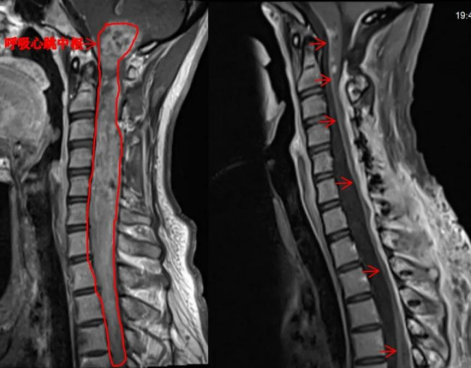

25岁的小周近年来逐渐出现下肢乏力、行走困难等症状,近期在外院就诊发现患上了NF2相关的神经鞘瘤病,检查提示其颅内、脊髓、脊椎旁多发肿瘤,其中脊髓内病变从高颈段延伸至第五胸椎水平,长度大约30公分,脑干内病变及高颈段病变位于心跳和呼吸中枢附近,手术风险极高,随后,到中大五院神经外科进行手术治疗。

刘飞主任表示,脊髓和脑干的室管膜瘤是造成患者主要症状的原因,此类肿瘤生长比较缓慢。而手术又涉及脑干这一“生命中枢”,一旦受到损伤,患者当即会出现心跳、呼吸停止;脑干周围还分布着许多重要的神经血管,包括动眼神经、面神经、三叉神经、迷走神经等,操作难度极大,手术中1毫米的差错都有可能造成不可逆的神经损伤。